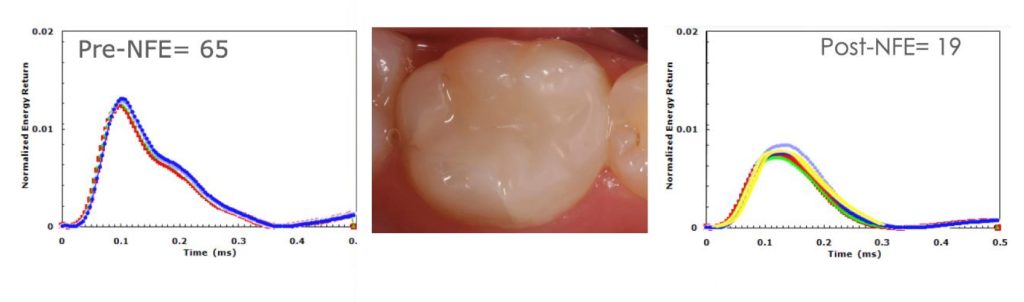

Case 1: Leaking restoration and tooth fracture

Tooth #30 in a 22-year-old woman was slightly sensitive to cold. Radiographs did not show a significant problem, but the ERG (Fig. 2) showed an abnormally shaped graph with a rating of 65. The filling was removed, revealing a leaking alloy marginal opening, with gross decay across the entire intaglio surface of the filling and a tooth fracture on the pulpal floor that ran halfway from the distal marginal ridge to the center of the tooth.

After replacing the leaking restoration with a composite restoration, another QPD measurement was taken and the tooth now registered a rating of 19 (Fig. 3).

(Six years later, the patient moved back to the area and the tooth was tested again. It stabilized at a rating of 21 with no further treatment.)